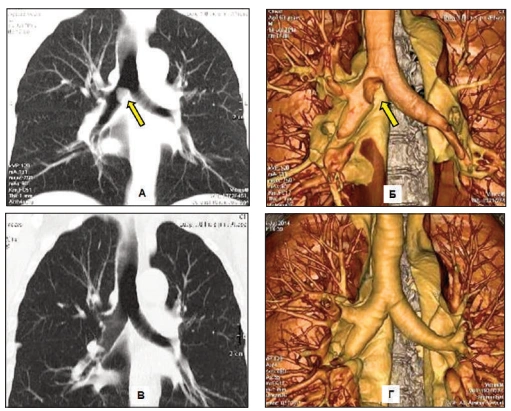

Routine tests miss the "respiratory evil" that Dr. Carson identifies in his functional medicine practice: A dense, hardened layer of old mucus and toxins (PM2.5, tar, heavy metals) that glues the air sacs (alveoli) shut.